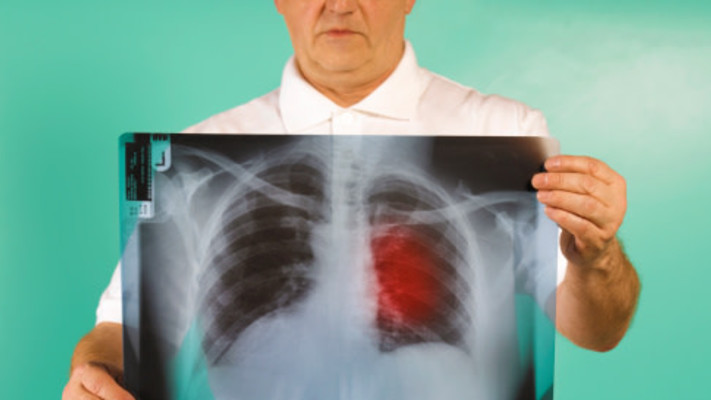

ד"ר מושקוביץ מסבירה שבזכות ההתקדמות בחקר הסרטן, בחלק מהמקרים כשמתגלות מוטציות מסוימות בגידול, ניתן להתאים טיפול מוכוון מטרה, ובכך לעכב את התקדמות המחלה ולאפשר הארכת חיים משמעותית למטופלים. "יש לנו כיום טיפולים חדשניים מכוונים למוטציות ספציפיות, שמניעות את השגשוג וההתקדמות של הגידול" היא אומרת. "על מנת לאתר את קיומן של אותן מוטציות, מבצעים בדיקה גנומית שנלקחת מרקמת הגידול של החולה. במקרים מסוימים, אין מספיק חומר לבדיקה או שדגימת הגידול ע"י ביופסיה קשה או מסוכנת למטופל, שכן מדובר בבדיקה פולשנית, ואז אנו מבצעים ביופסיה נוזלית ( מדגימת דם ) בשיטות שונות,

כמו למשל בדיקת "גארדנט 360" (Guardant360). במעבדה מתבצע תהליך בו מופרד הדנ"א החופשי בזרם הדם משאר הרכיבים והוא עובר תהליך סריקה לאיתור מוטציות הקשורות להנעת הגידול הסרטני ומהוות מטרות לטיפול".

בדיקת "גארדנט 360" מוצעת לא רק לחולים שזקוקים להתאמת הטיפול לאחר אבחון מחלתם, אלא גם לחולים שכבר מטופלים בתרופות ממוקדות מטרה ,אך נמצאים בשלב שהגידול פיתח עמידות לטיפול שהם מקבלים, ומחלתם מתקדמת. "במקרים מסוימים מתפתחת עמידות לתרופות ובשלב זה אנו עוברים לרוב לטיפול אחר, בעיקר כימותרפיה", אומרת ד"ר מושקוביץ, "עם זאת, במקרים מסוימים אנו ממליצים לבצע בדיקת 'גארדנט 360' במטרה לגלות האם התפתחה מוטציה נוספת שגורמת לשגשוג של המחלה, ולעיתים נוכל להתאים טיפול מכוון מטרה אחר".

הביופסיה הנוזלית מסוג "גארדנט 360" יכולה לסייע למטופלים עם סוגי גידולים שונים למציאת חלופות טיפוליות מותאמות אישית עבורם. הבדיקה מזהה מוטציות במקטעי דנ"א חופשי של הגידול הנמצאים אפילו בשכיחות נמוכה מאוד. הבדיקה נחשבת לרגישה במיוחד. מחקרים הראו כי לבדיקה זו אמינות גבוהה, עם יכולת זיהוי מוטציות ביעילות של 99.99%

כאשר מתקבל ממצא חיובי של נוכחות מוטציה בבדיקת "גארדנט 360", התוצאה מספיקה בשביל להתחיל טיפול ממוקד או להצטרף למחקר קליני בהתאם לקריטריונים, לרוב ללא צורך באישוש של הממצא בבדיקה מבוססת רקמה. אם אין למטופל מספיק חומר לביצוע פרופיל מולקולרי, השימוש בבדיקת "גארדנט 360" חוסך מהמטופל את הצורך לעבור ביופסיה פולשנית נוספת הכרוכה לעיתים בסיכונים, אי נעימויות או עיכוב בתחילת הטיפול.